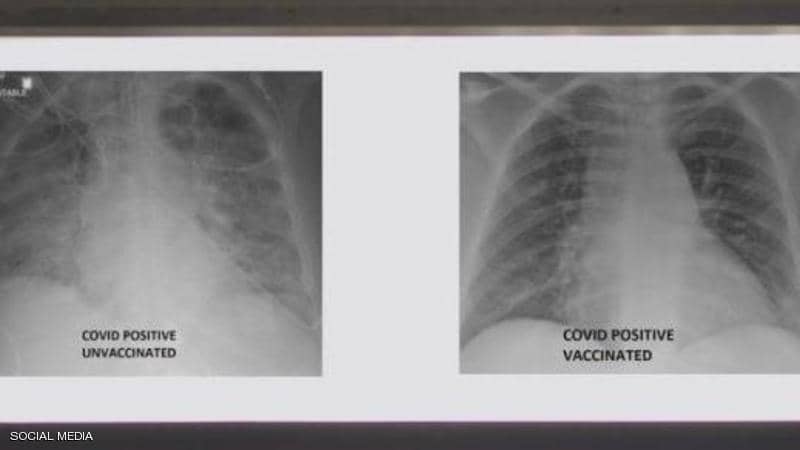

نشر الطبيب العربي في الولايات المتحدة غسان كمال، صورة تظهر الفرق بين رئتي شخص جرى تطعيمه ضد فيروس كورونا ورئتي شخص آخر لم يتلق التطعيم، مشيرا إلى أن الاثنين أصيبا بفيروس كورونا.

وأظهرت صور الأشعة السينية أن رئتي الشخص غير الملقح، المصاب بفيروس كورونا كانت بيضاء بصورة شبه كاملة وتعرف بـ"عتامة الرئة"، مما يعني أنها كانت غارقة في الفيروس، في حين أبرز صور رئتي الشخص ببيضاء أقل.

وتعني صورة الأول أيضا نقصا في دخول الهواء إلى رئتيه، فيما تعني لدى الثاني أن الهواء يتدفق بسهولة علاوة على أن رئتيه خاليتين من الوباء.

وأشار إلى أنه نشر الصور من أجل إظهار الفرق الذي يمكن أن يحدثه اللقاح في رئتي الشخص في حال إصابته بالفيروس.